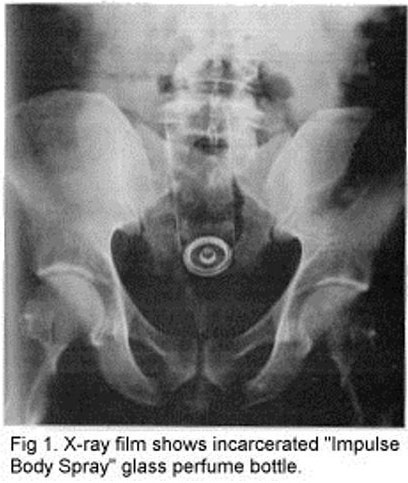

Confira 20 coisas que você não vai acreditar que as pessoas colocaram no ânus. Todos os casos foram comprovados por radiografias. É realmente estranho!!

10 – Lata de spray – Acredite se quiser, alguém colocou uma lata de spray no traseiro.